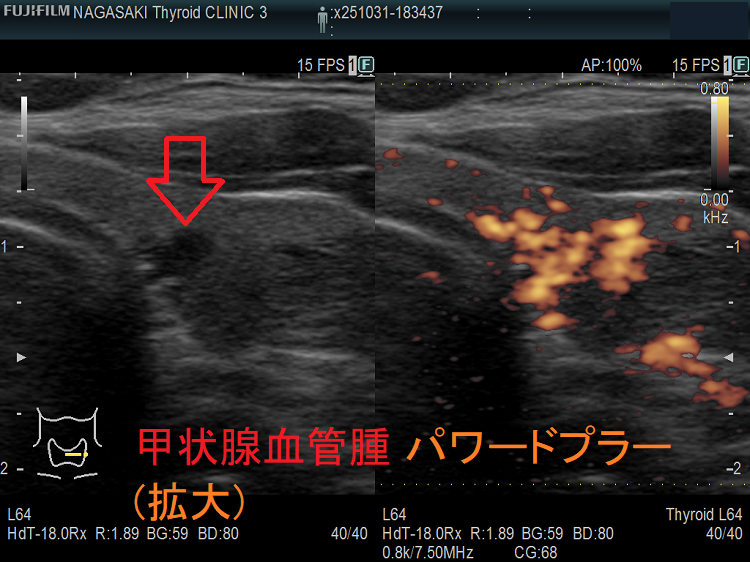

甲状腺に発生する血管腫は非常に稀で、日本の報告例もわずかです(日臨外会誌 72(3),579―583,2011)。

甲状腺血管腫(拡大) ドプラーモード(eFlow);腫瘍内血管が3次元的に見え、毛玉の様。

ケース④